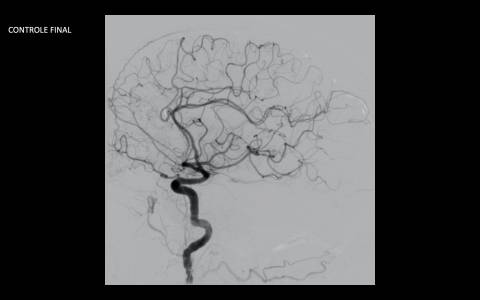

Realizado angiografia cerebral e reconstrução 3D sendo evidenciado um aneurisma de colo largo com ramo frontal emergindo do colo do aneurisma. Baseado nessas característica, foi optado por tratamento com stent redirecionado de fluxo Fred Jr., associado a micromolas de platina devido o importante inflow do ramo frontal.

Feito duplo acesso femoral e cateterismo da carótida esquerda, seguido de microcateterismo distal ao aneurisma com Headway 21 para o implante do stent, bem como do saco aneurismático para a deposição das micromolas.

Implantado um stent 2,5 x 18mm conforme programação 3D. O procedimento transcorreu sem intercorrência, mantendo a patência dos vasos envolvidos.